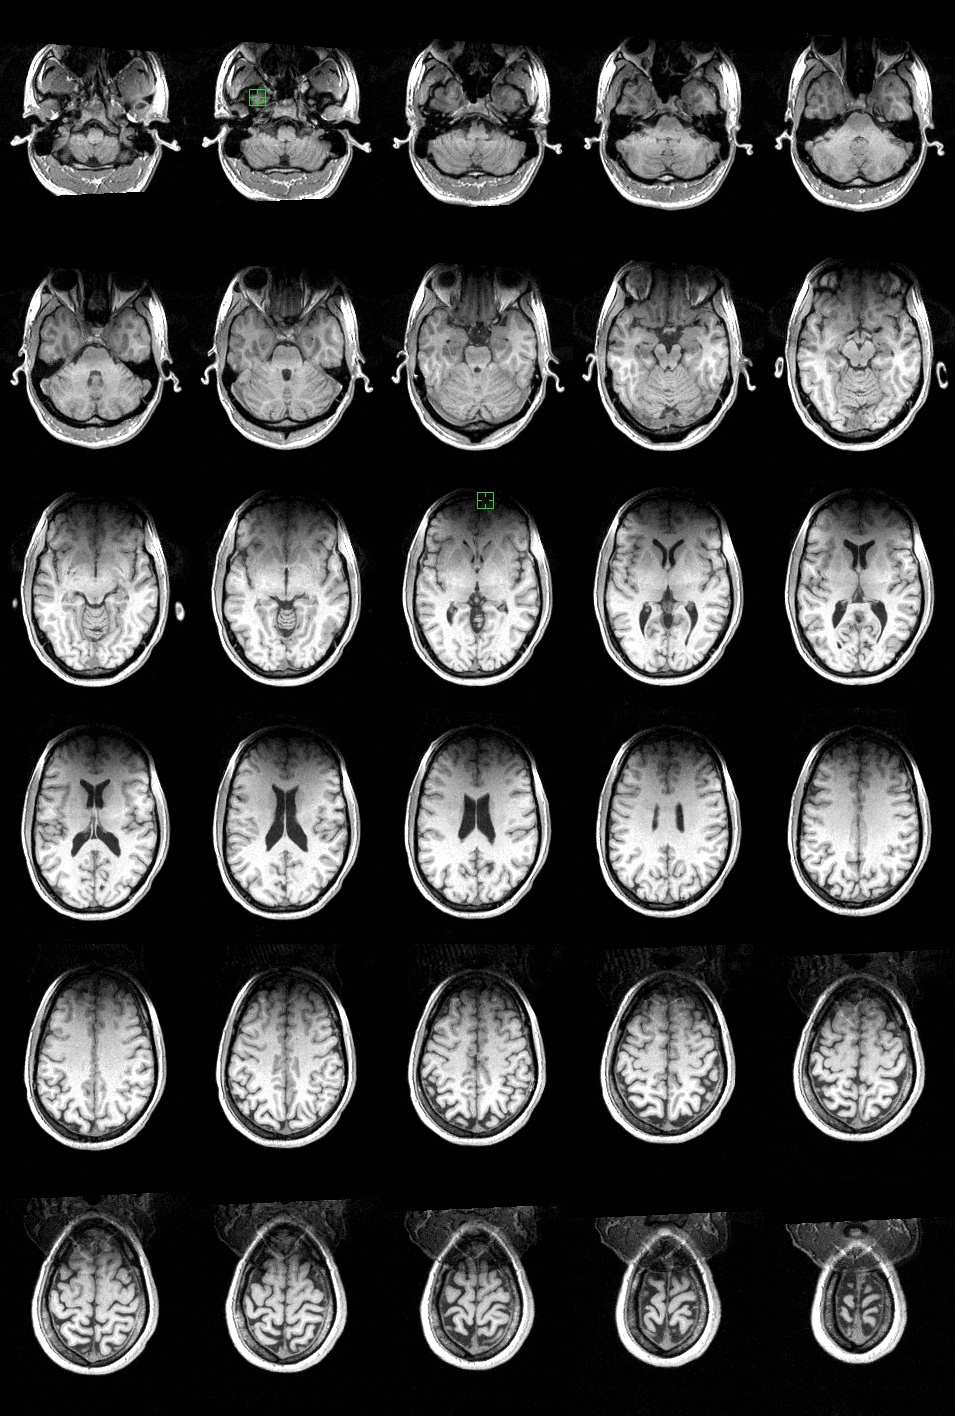

Axial slices: These images go from the inferior in the upper left to superior in the lower right. Here the left side of the image represents the left side of the brain. |